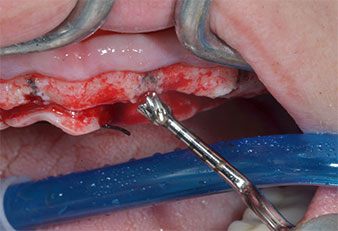

Ein flammenförmiges, diamantiertes piezochirurgisches Instrument (Piezomed I1) wurde verwendet, um die Implantatpositionen zu markieren und die Pilotpräparationen durchzuführen (Abb. 3). Dabei wurde darauf geachtet, eine Auf- und Abbewegung mit reduzierter Leistung, voller Spülung und niedrigem Druck (unter 300 g) anzuwenden. Als Nächstes wurde ein Pilotinstrument (Piezomed I2A/I2P) zur initialen Erweiterung der Implantatlager auf einen Durchmesser von 2 mm verwendet (Abb. 4), gefolgt von einem 3-mm-Instrument (Abb. 5).

Bei dichtem Knochen sollte das gesamte Set, einschließlich der Zwischeninstrumente Piezomed Z25P und Z35P verwendet werden, um die Osteotomien vor dem nächsten Schritt zu erweitern.

Diese Instrumente sind auch für die Aufbereitung bei interner Sinusbodenaugmentation in der Nähe der Sinusmembran indiziert oder wenn weniger als 4 mm Restknochenhöhe verbleibt.

Im vorliegenden Fall wurden die Instrumente Z25P und Z35P wegen des relativ weichen posterioren Knochens nicht verwendet, der problemlos mit dem I3A/I3P bearbeitet werden konnte.

Wegen des relativ harten Knochens (D2) an den Positionen 11 und 21 wurden die 10 mm langen Implantatlager in diesem Bereich abschließend mit einem 4-mm-Spiralbohrer, dem chirurgischen Winkelstück WS-75 L von W&H und dem W&H Implantmed Implantologiemotor in Verbindung mit dem optionalen W&H Osstell ISQ module präpariert. Im Gegensatz dazu wurde der weiche Knochen der Implantatlager im Seitenzahnbereich mit dem Piezomed I3P auf den abschließenden Durchmesser von 3 mm erweitert. Die Implantate wurden dann transgingival eingesetzt, die Einheildauer betrug drei Monate (Abb. 6-10). Die vorhandene Prothese wurde auf vier provisorischen Implantaten abgestützt (Abb. 8).